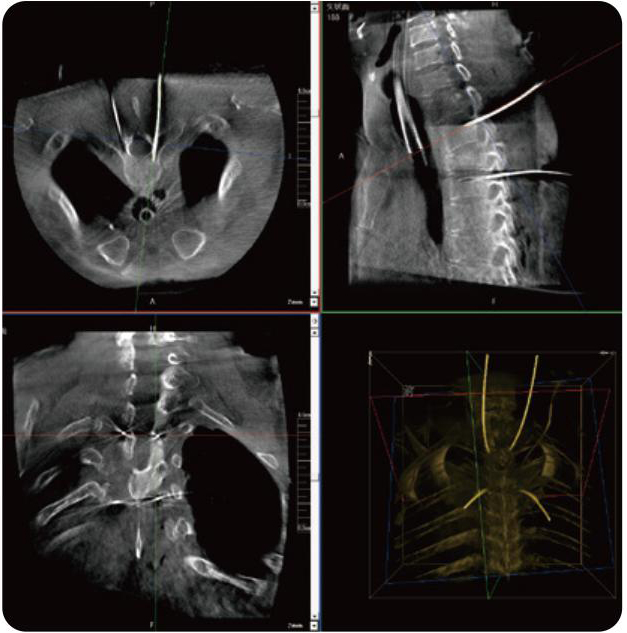

PL300B可應用于多節段脊柱外科手術(shù),輔助醫生定位病灶部位,為脊柱外科手術(shù)(經(jīng)皮椎體成形術(shù)、椎弓根螺釘內固定術(shù)等術(shù)式)提供術(shù)前手術(shù)流程規劃、入釘位置、角度可視化引導,模擬仿真入釘輔助。

PL300B搭配普愛(ài)醫療自主研發(fā)生產(chǎn)的平板3D C形臂,借助一體化自適應配準( 軌跡配準)技術(shù),通過(guò)追蹤C形臂三維采集軌跡,自動(dòng)完成圖像坐標建立和系統坐標配準。配準精度更高,操作步驟少,系統運作效率高。